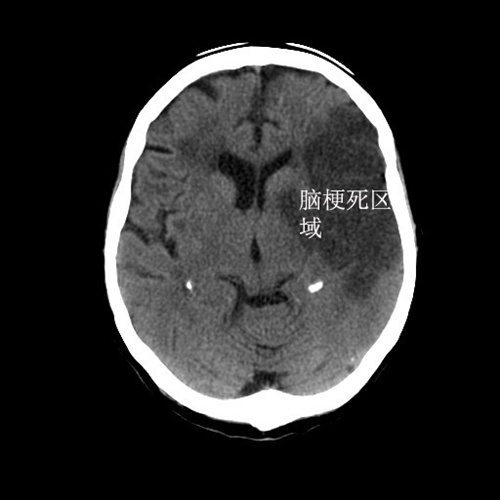

看着这位既往患有20年高血压,现在血压为160/90mmHg的老人,我非常担心会不会是急性脑梗死或者脑出血。不仅是因为老人上一次脑梗塞时也是同样的症状,更加是因为老人已经开始出现右侧肢体肌力降落!

最后检查结果果然提示导致老人出现头痛欲吐的罪魁祸首:脑梗塞!最后这位老人住进了神经内科病房,经过十余天的治疗后康复出院!